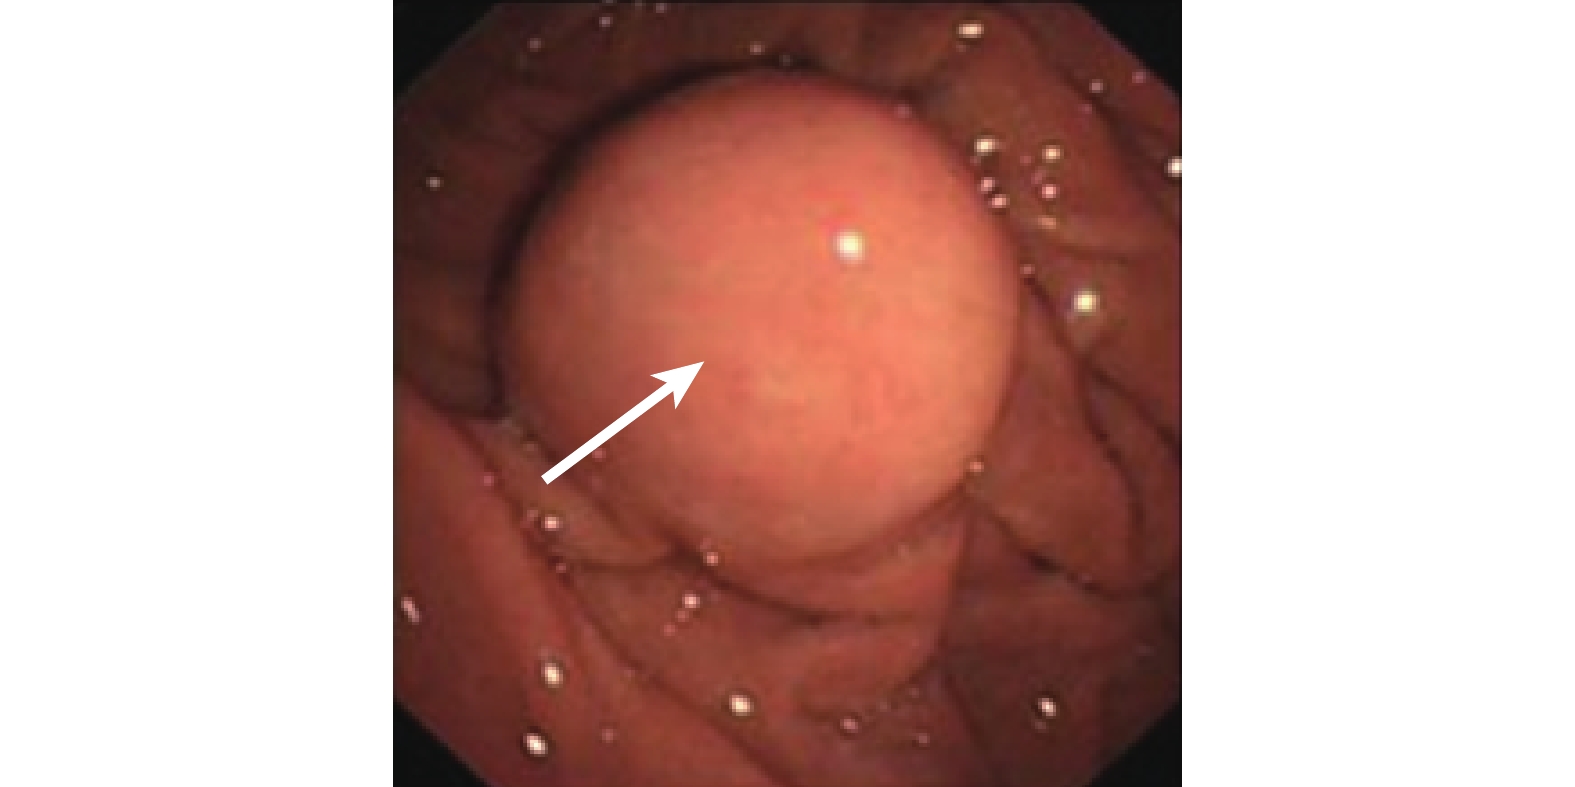

直腸間質瘤在結腸鏡下均表現為扁平黏膜隆起,表面光滑,形態尚規則,基底部寬(圖 1)。本組 29 例患者行 CT 或 MRI 檢查,表現為盆腔邊界清楚的軟組織腫塊,主要為黏膜下、肌間層或漿膜下的圓形或分葉狀腫塊,其向腸腔內、外突出生長,直腸可呈不同程度地受壓和變窄,腫瘤密度及信號不均,可見壞死、鈣化和出血;增強掃描時腫瘤邊緣帶可呈中等程度結節樣強化,腫塊中心部分無強化,呈壞死樣改變(圖 2)。

直腸間質瘤的確診尚需依賴病理學檢查,但因解剖位置特殊及取材困難,術前不利于確診。直腸間質瘤多發生于直腸的中低位,直腸指診可對腫瘤的位置、大小、質地和活動度作出直觀判斷。因此,直腸指診對于直腸間質瘤的早期檢出和鑒別診斷具有不可忽視的作用[7]。本組 33 例患者均行直腸指檢,觸及腫物 23 例,指套取出可見血;結腸鏡下見腫物形狀尚規則,黏膜多光滑。